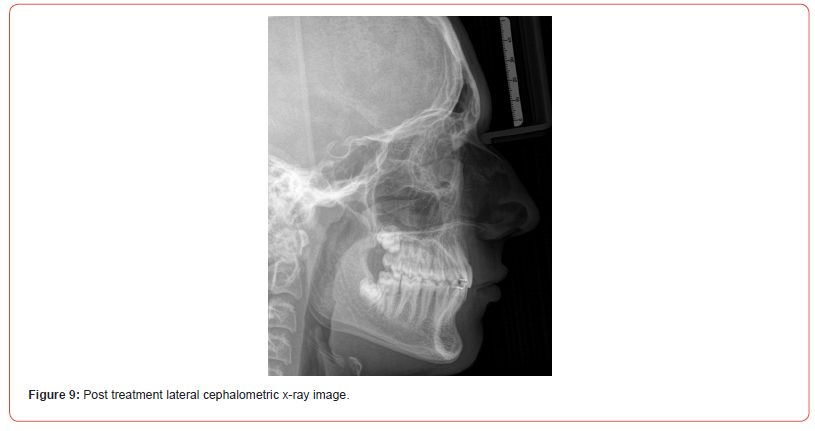

The case was finished with the canines and molars on the righthand side in class I relationship. The left maxillary first premolar was adjusted with composite to resemble a canine and finished in class I occlusion good gingival zenith, and the molar on the lefthand side in a full unit class II (Figure 6). The case was finished with a balanced, functional occlusion and favorable facial aesthetics (Figure 7).